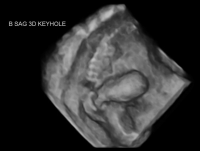

Luto 3D sagittal keyhole bladder

Lower urinary tract obstruction (LUTO) refers to a blockage in the urinary tract that restricts or prevents the release of urine from the bladder. Accumulation of urine within the kidneys and bladder throughout pregnancy results in permanent damage to these organs. If urine cannot exit the body, the amount of surrounding amniotic fluid decreases. Amniotic fluid is essential for normal lung development. LUTO occurs in about one in 5,000 births.

Kidney and bladder findings and amniotic fluid volume are monitored with ultrasound in pregnancies complicated by LUTO. In selected cases, in utero therapy via vesicoamniotic shunt placement may be discussed. Briefly, this involves placement of a shunt, or small tube, to connect the fetal bladder with the surrounding amniotic fluid.